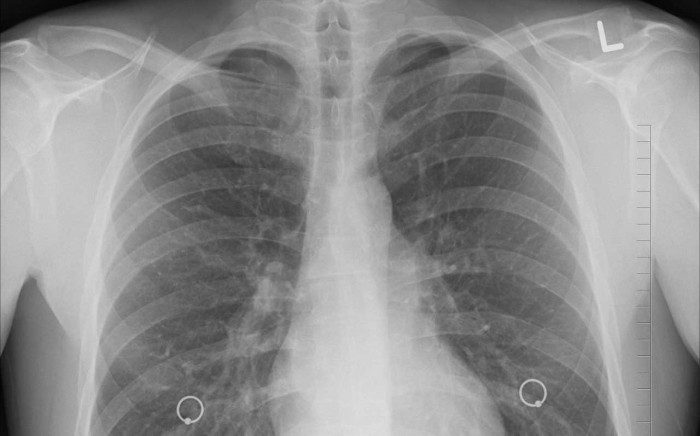

用于创建支架的3D打印过程被称为数字光处理,并使用专门为此目的调整的光敏树脂。该过程要求研究人员创建一个特定部分气道的计算机断层扫描图像,在将数据传输到DLP打印机之前,该图像用于开发支架的3D模型。